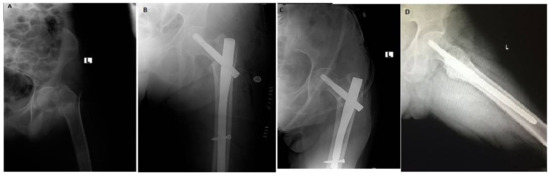

Functional and Radiological Results of Proximal Femoral Nail Antirotation (PFNA) Osteosynthesis in the Treatment of Unstable Pertrochanteric Fractures

3. Results